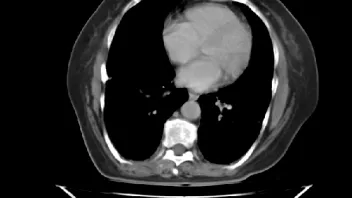

ist jemand unter Euch der sich auskennt mit CT Aufnahmen ?

Ich habe 3 Stück angehangen, sie stammen aus einem CT der Abdomen.

Möglich das es eine Serie eines Querschnitts darstellt Bild 1 zeigt den Start,Bild 2 eines aus den mittleren Aufnahmnen und Bild 3 das letzte dieser CT Serie.

Da ganz gezielt auf ein und die gleiche Stelle gehalten wurde mit sagenhaften über 80 Einzelaufnahmen interessiert mich brennend um die Darstellung welches Organges es sich bei diesen Aufnahmen handelt und ob darauf etwas bedenkliches eingekreist wurde.

Herzlichen dank für die Hilfe,falls jemand es einordnen kann. Mir ist die Antwort darauf so wichtig weil es sich um Aufnahmen meiner Mutter handelt die nicht mehr unter uns ist.